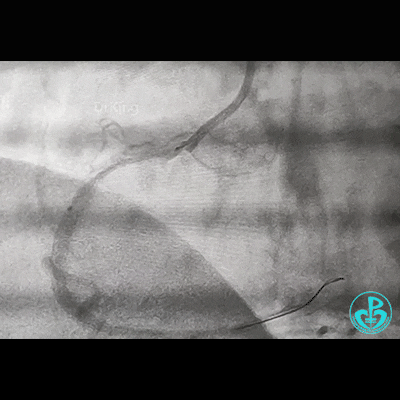

治疗过程

处理右冠,XB RCA,Sion、Sion blue导丝,2.0×20mm球囊。支架植入过程相当顺利,很快就完成,窃喜!心想后扩后马上结束!

植入3.5×29mm和3.5×24mm支架。